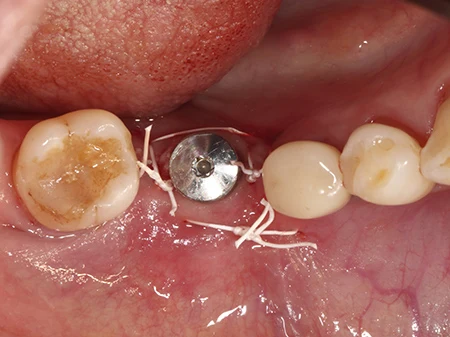

移植した骨に軟組織が入り込まないようにコラーゲンの膜で保護します。

キャップが歯ぐきから少しでた状態で縫合して終了です。骨の移植をした場合は2〜3ヶ月ほど待って型取りを行います。